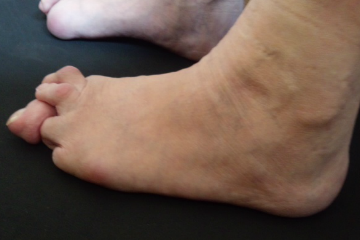

外反母趾は症状、変形、疼痛の痛みの具合は様々です。

外反母趾の問題は疼痛(とうつう)、痛みだけではありません。

・外反母趾の変形症状による身体を支える機能の低下、消失

・ハンマートゥ